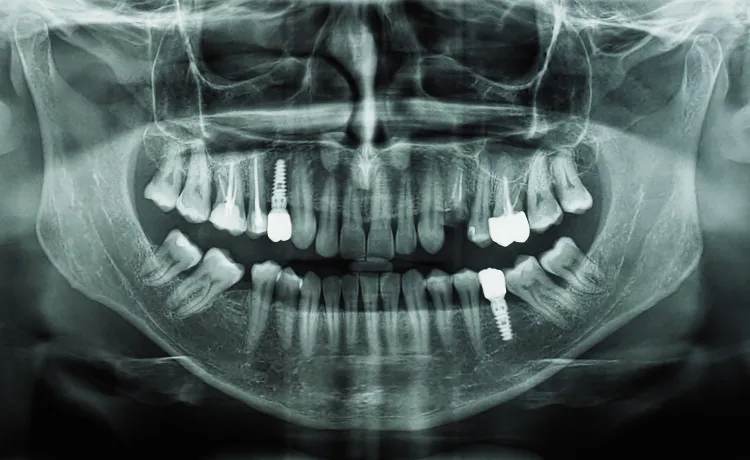

Ósemka usunięta: co dzieje się w łuku zębowym tuż po zabiegu?

Bezpośrednio po usunięciu ósemki, w miejscu po zębie powstaje pusta przestrzeń. Tkanki miękkie i kostne potrzebują czasu na zagojenie, ale już wtedy rozpoczynają się subtelne procesy adaptacyjne w całym łuku zębowym. Choć nie odczujesz tego z dnia na dzień, a zmiany nie są gwałtowne, to właśnie w tym momencie inicjowany jest wspomniany proces mezjalizacji. Sąsiednie zęby, a zwłaszcza siódemka, zaczynają odczuwać brak podparcia i nacisku, co stwarza warunki do ich powolnego przemieszczania się. Jest to początek reorganizacji sił w jamie ustnej, która może mieć różne konsekwencje dla Twojego zgryzu.

Ząb sąsiadujący bezpośrednio z usuniętą ósemką, czyli siódemka, może zareagować na utratę podparcia w sposób niekorzystny. Bez nacisku i stabilizacji ze strony ósemki, siódemka ma tendencję do przechylania się w stronę pustego miejsca. Takie przechylenie może prowadzić do zaburzeń zgryzowych, nieprawidłowych kontaktów z zębami przeciwstawnymi, a także utrudniać higienę, zwiększając ryzyko próchnicy i chorób przyzębia w tej okolicy.

Zjawisko Godona to problem, który może wystąpić, gdy usuniemy tylko jeden ząb mądrości, nie usuwając jego odpowiednika w przeciwległym łuku (antagonisty). Na przykład, jeśli usuniemy dolną ósemkę, a górna pozostanie, ząb górny, pozbawiony kontaktu z dolnym, zacznie się wysuwać z kości (ekstruzja). To zaburza równowagę zgryzową, prowadzi do nieprawidłowych kontaktów podczas żucia, może powodować przeciążenia, a nawet problemy ze stawem skroniowo-żuchwowym. Dlatego często zaleca się usunięcie obu zębów mądrości z danej strony, aby zapobiec temu zjawisku i utrzymać prawidłową równowagę w zgryzie.